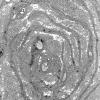

1K4B Massive Onion Bulbs (Case 1) EM 016 - Copy copy

1K4C Massive Onion Bulbs (Case 1) EM 017 - Copy

1K4D Massive Onion Bulbs (Case 1) EM 075 - Copy

1K4E Massive Onion Bulbs (Case 1) EM 020 - Copy

1K4F Massive Onion Bulbs (Case 1) EM 019 - Copy

1K4G Massive Onion Bulbs (Case 1) EM 064 - Copy

1K4H Massive Onion Bulbs (Case 1) EM 068 - Copy

1K4I Massive Onion Bulbs (Case 1) EM 073 - Copy

1K5A Massive Onion Bulbs (Case 1) EM 084 - Copy

1K5B Case 1_086 - Copy

1K5C Massive Onion Bulbs (Case 1) EM 88 - Copy

1L1 Massive Onion Bulbs (Case 1) EM 089 - Copy